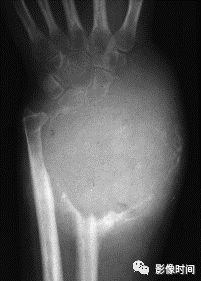

(一)地图样破坏  地图样破坏是指肿瘤组织在一个局部呈团块状生长造成界限清楚的骨质破坏(图 1、图 2、图 3、图 4)。

病灶可位于骨的中心或一侧部位,呈圆形、卵圆形密度减低区,与正常骨质分界清晰,边缘可有或无硬化带围绕,骨的形态无变化,病灶内可完全透亮或可见粗细不均、大小不等的残留骨嵴,内缘可光滑或呈分叶状压迹。

地图样破坏见于大多数良性肿瘤和肿瘤样病变如单纯性骨囊肿、骨纤维结构不良、血管瘤等、也可见于部分恶性骨肿瘤如骨转移瘤、骨髓瘤等。

图 3  地图样破坏:骨内脂肪瘤